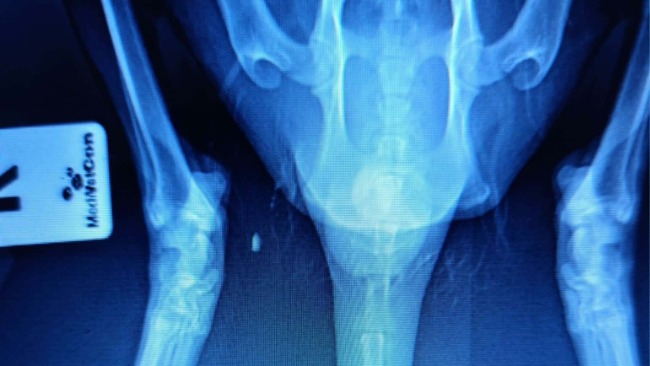

Przyczyn niedowładu mogło być wiele, więc wykonaliśmy wszystkie niezbędne badania - wykluczyliśmy Toxoplazmozę, wykonaliśmy badania krwi, sprawdziliśmy kotka też pod kątem FIP. Kluczowa okazała się diagnostyka obrazowa - zdjęcie RTG które wykazało dwa duże ropnie przy kręgosłupie, w okolicy ogona, uciskające na nerwy i uniemożliwiające mu chodzenie. Ropnie zostały dokładnie oczyszczone, a rana już po kilku dniach zaczęła pięknie się goić.

Mruczuś ZNÓW CHODZI! Już nie powłóczy łapami, porusza się pewnie i lekarze są bardzo zadowoleni z efektów leczenia. Przy pierwszym badaniu ważył tylko 2,6 kg. Dziś — po leczeniu i opiece — waży 3,4 kg. To ogromna różnica jak na tak krótką chwilę.